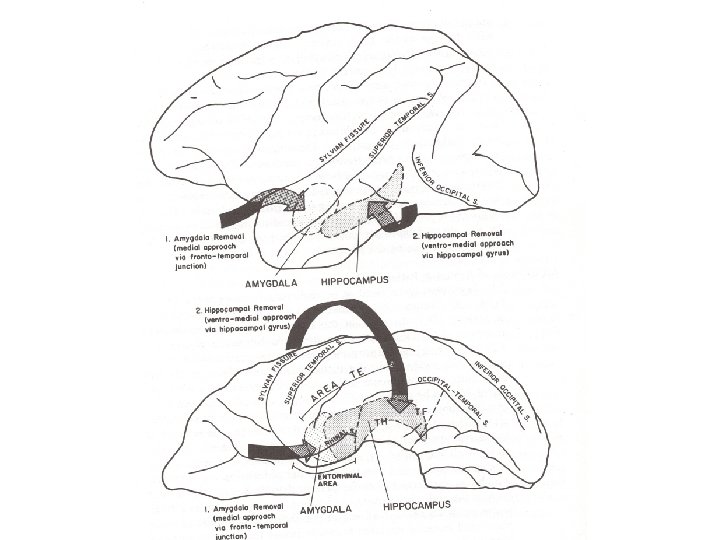

Zola-Morgan & Squire, 1990

Zola-Morgan & Squire, 1990